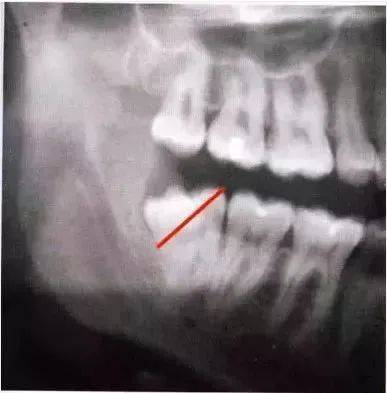

全颌曲面断层×线片。切割牙冠时应经过阻生牙远中面的牙颈部的釉牙骨质交界处。

下颌升支前缘的骨吸收区有利于牙片的取出。